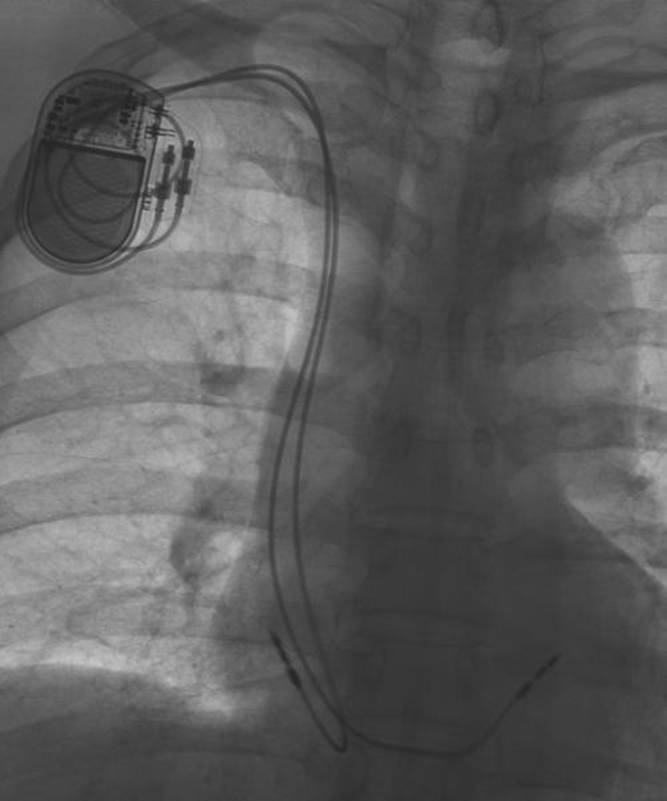

PM除去⇒体外ペーシング(感染の有無検査で1週間寝たきり)

さて今日は除去、そして体外式ペーシングの取り付け、二度目である。只今回は除去後の経過を見るためである。

手術用の体外式ペーシング(MEDTRONIC5375

DEMAND PULSE GENERATOR) が、35 PPMに設定されている。

自己脈はほぼ42前後で安定している。この配線が右頚から静脈を経て心臓に当てられている。

それと、テレメトリー式心電送信機(心電・呼吸送信機)の三本線が、身体に貼り付けられている。ナースセンターで四六時中監視しているのだ。まぁ、ペースメーカー植え込んだ時点で自分もコンピュータ化されてしまった。

201201241835

201201241837